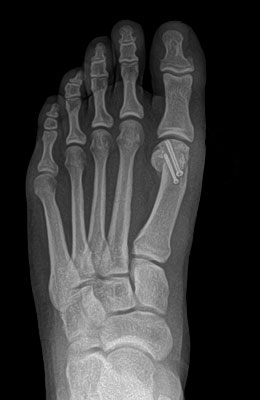

Minimally Invasive Bunion Surgery featuring the miniBunon™ System and Tailors Bunionectomy